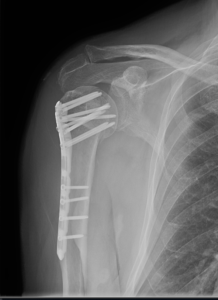

if the fracture is displaced, surgery may be needed to put the bone back into the correct position and fix the bone with Plates & screws or nails for adequate healing to occur.

- Shoulder Fractures.

- Clavicle Fractures.